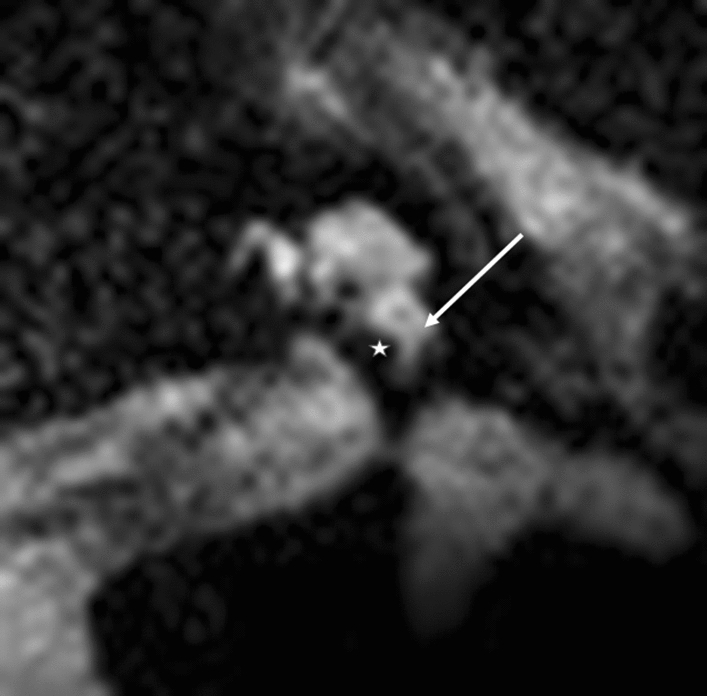

Figure 3.

Modiolar electrode, basal turn, HFMS. Star represents diminishing electrode signal, arrow represents basilar membrane.

Modiolar electrode characteristics allowed us to visualize a lateral T2 signal from the electrode at the basal turn and a basilar membrane pattern (Figs. 3 and 4). This basilar membrane pattern allowed us to locate the electrode in the scala tympani definitely.